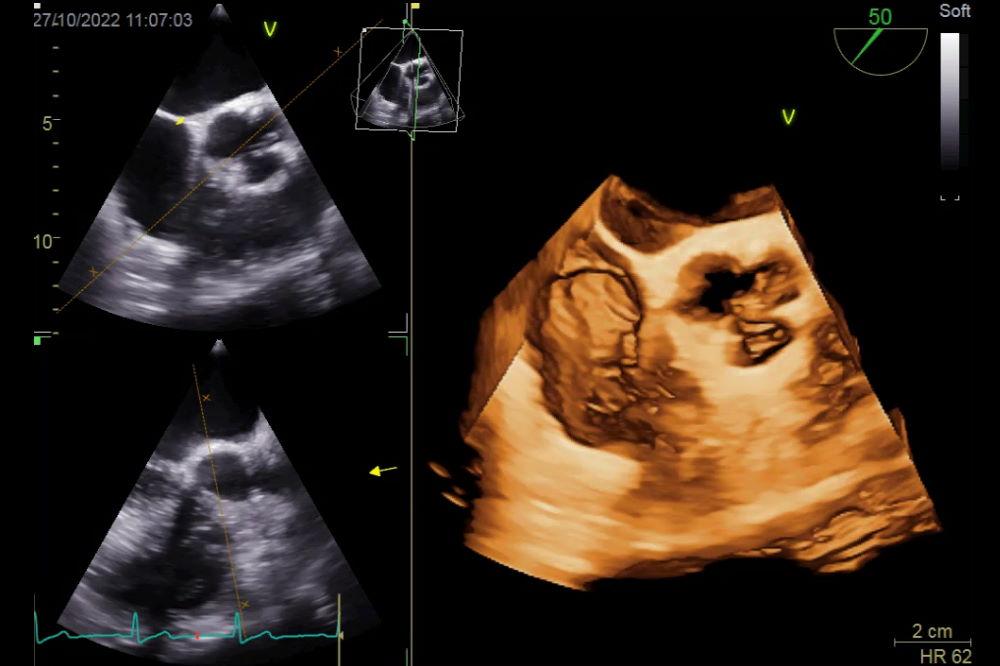

Η τεχνολογία του διαθωρακικού υπερηχοκαρδιογραφήματος (ΔΥΚ) αποτελεί μια επαναστατική προσέγγιση στην μελέτη της καρδιάς, επιτρέποντας στους γιατρούς να αποκτήσουν λεπτομερείς εικόνες της καρδιακής δομής και λειτουργίας. Μέσω ηχητικών κυμάτων υψηλής συχνότητας, οι ειδικοί μπορούν να ανακαλύψουν ανατομικές λεπτομέρειες που προηγουμένως ήταν αόρατες ή δύσκολα προσβάσιμες. Αρκετοί παράγοντες συμβάλλουν στη χρησιμότητα αυτής της μεθόδου, όπως:

- Εικόνα σε πραγματικό χρόνο: Παρέχει ζωντανές εικόνες της καρδιάς καθώς λειτουργεί.

Το ΔΥΚ επιτρέπει επίσης την εκτίμηση της λειτουργίας των καρδιακών θαλάμων και δεικτών όπως η καρδιομυϊκή συσπάση και η εκπαίδευση της καρδιάς. Η ικανότητα να παρακολουθούμε τη ροή του αίματος και την καρδιοαγγειακή πίεση παρέχει κρίσιμες πληροφορίες για τη διάγνωση και παρακολούθηση ασθενειών. Ένα συγκριτικό πλεονέκτημα είναι η δυνατότητα αξιολόγησης πολλών παραμέτρων σε πραγματικό χρόνο:

** Απάντηση** Η διαδικασία του διαθωρακικού υπερηχοκαρδιογραφήματος είναι σχετικά απλή και συνήθως διαρκεί περίπου 30 με 60 λεπτά. Ο ασθενής τοποθετείται σε ύπτια θέση, ενώ ο γιατρός εφαρμόζει ένα ειδικό gel στο στήθος του ασθενούς για να διευκολύνει τη μετάδοση των υπερήχων. Στη συνέχεια, ο υπερηχογράφος, μια συσκευή που παράγει και ανιχνεύει τους υπερήχους, τοποθετείται σε διάφορες θέσεις στο στήθος, προκειμένου να ληφθούν οι απαραίτητες εικόνες. Είναι σημαντικό να σημειωθεί ότι η διαδικασία είναι ανώδυνη και δεν απαιτεί αναισθησία.

Κατά τη διάρκεια της εξέτασης, ο γιατρός μπορεί να αξιολογήσει διάφορες πτυχές της καρδιάς, όπως τη λειτουργία των καρδιακών βαλβίδων, την καρδιομυϊκή λειτουργία και την παρουσία υγρού στην περικαρδιακή κοιλότητα. Επιπλέον, το triplex καρδιάς μπορεί να παρέχει πληροφορίες σχετικά με την καρδιοαγγειακή υγεία του ασθενούς, όπως η παρουσία στεφανιαίας νόσου ή καρδιομυοπάθειας. Αυτές οι πληροφορίες είναι κρίσιμες για τη διάγνωση και την παρακολούθηση της καρδιολογικής κατάστασης του ασθενούς.